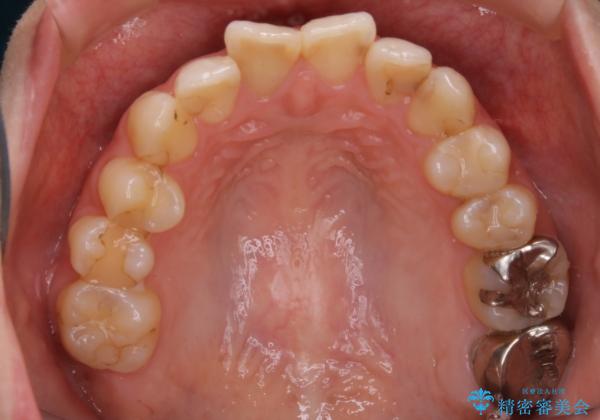

当院では矯正治療を主訴にご来院された方は治療開始前に必ず精密検査を受けていただきます。

ご本人は症状もなくご自覚がなくても実は歯周病が進行していたり、根管治療が必要な歯が見つかるということもあります。

基本的にはそういった歯周病・虫歯に対しての治療は矯正治療開始前に完治させておく必要があります。これは、矯正装置装着後は清掃不良になりやすく虫歯の進行が早まったり、歯を移動させることで歯周病や根尖病巣が悪化する恐れがあるためです。